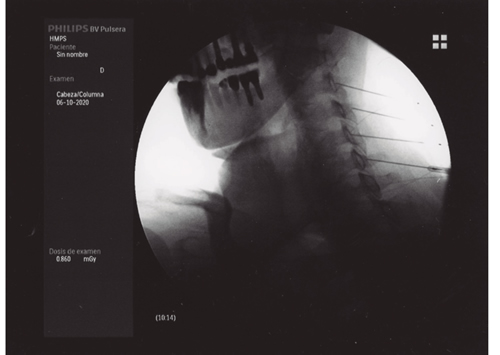

La neurotomía por radiofrecuencia del ramo medial es una técnica que está bien estandarizada a nivel cervical y lumbar, no así a nivel torácico, y que es un tratamiento que está bien establecido y estudiado con un nivel de evidencia alto (2,3,4). Por tanto, tras llegar al diagnóstico de dolor facetario el tratamiento de elección es la neurotomía por radiofrecuencia del ramo medial (Figuras 1 y 2).

Fig. 1.

Fig. 2.

La neurotomía por radiofrecuencia del ramo medial es una técnica estandarizada a nivel cervical y lumbar, con unos niveles de evidencia elevados y, por tanto, totalmente recomendable en el tratamiento del dolor facetario secundaria a la artrosis vertebral.